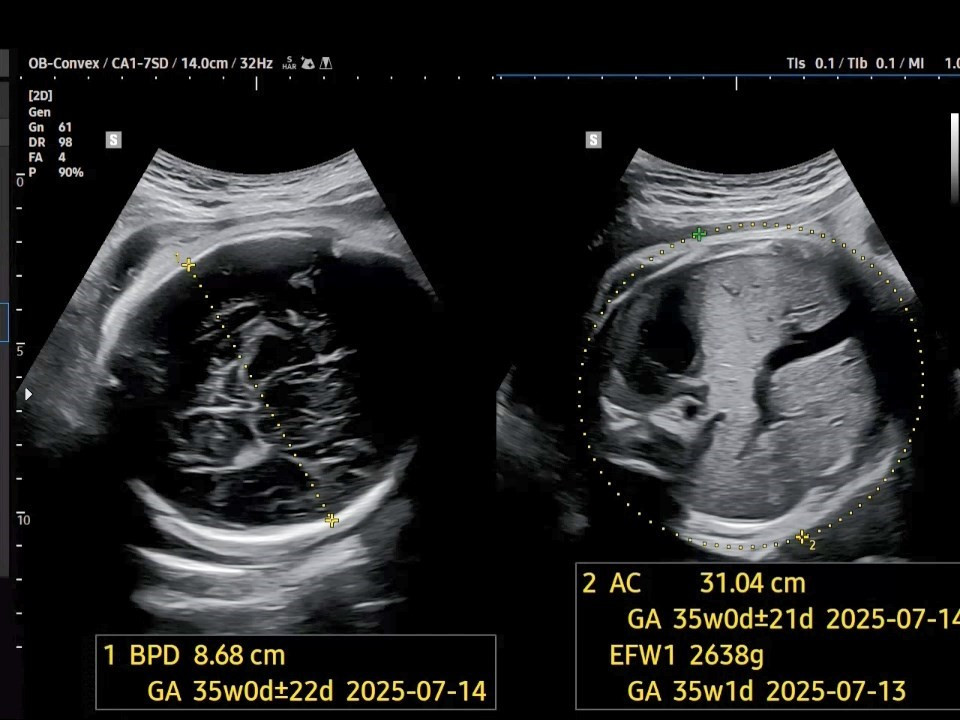

2. 태아 머리직경(BPD: Biparietal Diameter)은 8.68㎝이고, 태아 복부 둘레(AC: Abdominal Circumference)는 31.04㎝이네요. 두 수치 모두 35주 차의 크기라고 되어 있으니 약 2주 정도 차이가 나고 있습니다.

37주 BPD.jpg [37주 차 머리직경과 복부 둘레]